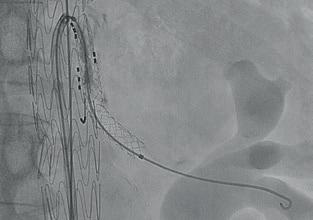

Precise implantation

Exact location and post-expansion